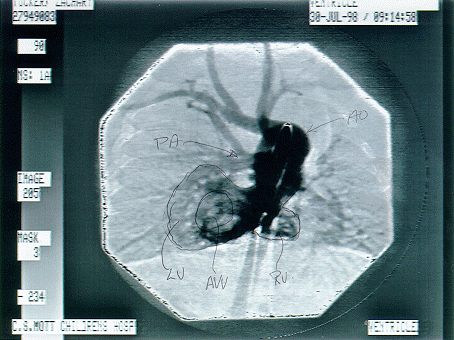

Zach's Heart

Because Of The Position, The Heart Was First Incorrectly Label As A Hypoplastic RIGHT Heart Instead Of Left